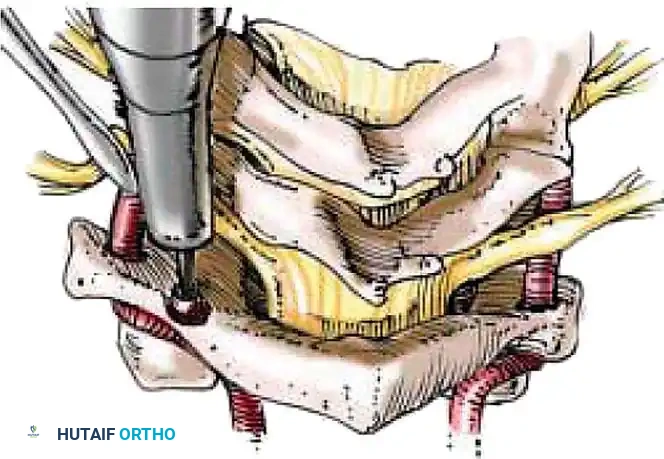

1. Exposure: Retract the longus colli muscles laterally to expose the anterior vertebral bodies and the damaged disc space.

2. Discectomy: Perform a complete discectomy using curettes and pituitary rongeurs. In trauma, the PLL is often torn; carefully remove any extruded disc fragments compressing the cord.

3. Endplate Preparation: Decorticate the cartilaginous endplates using a high-speed burr to expose bleeding subchondral bone, ensuring a robust fusion bed.

4. Grafting: Insert a structural allograft or PEEK cage packed with autograft/demineralized bone matrix (DBM) into the disc space.

5. Plating: Apply a rigid anterior cervical plate. Ensure screws are placed parallel to the endplates and do not breach the adjacent disc spaces.